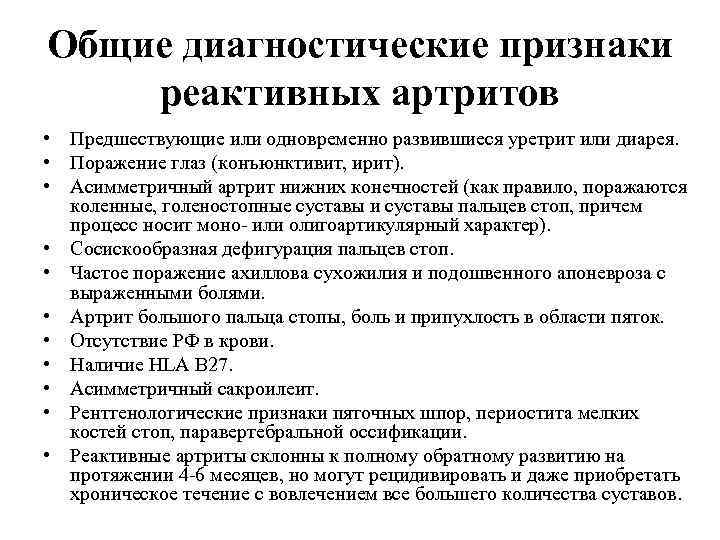

Общие диагностические признаки реактивных артритов • Предшествующие или одновременно развившиеся уретрит или диарея. • Поражение глаз (конъюнктивит, ирит). • Асимметричный артрит нижних конечностей (как правило, поражаются коленные, голеностопные суставы и суставы пальцев стоп, причем процесс носит моно- или олигоартикулярный характер). • Сосискообразная дефигурация пальцев стоп. • Частое поражение ахиллова сухожилия и подошвенного апоневроза с выраженными болями. • Артрит большого пальца стопы, боль и припухлость в области пяток. • Отсутствие РФ в крови. • Наличие HLA B 27. • Асимметричный сакроилеит. • Рентгенологические признаки пяточных шпор, периостита мелких костей стоп, паравертебральной оссификации. • Реактивные артриты склонны к полному обратному развитию на протяжении 4 -6 месяцев, но могут рецидивировать и даже приобретать хроническое течение с вовлечением все большего количества суставов.

Общие диагностические признаки реактивных артритов • Предшествующие или одновременно развившиеся уретрит или диарея. • Поражение глаз (конъюнктивит, ирит). • Асимметричный артрит нижних конечностей (как правило, поражаются коленные, голеностопные суставы и суставы пальцев стоп, причем процесс носит моно- или олигоартикулярный характер). • Сосискообразная дефигурация пальцев стоп. • Частое поражение ахиллова сухожилия и подошвенного апоневроза с выраженными болями. • Артрит большого пальца стопы, боль и припухлость в области пяток. • Отсутствие РФ в крови. • Наличие HLA B 27. • Асимметричный сакроилеит. • Рентгенологические признаки пяточных шпор, периостита мелких костей стоп, паравертебральной оссификации. • Реактивные артриты склонны к полному обратному развитию на протяжении 4 -6 месяцев, но могут рецидивировать и даже приобретать хроническое течение с вовлечением все большего количества суставов.